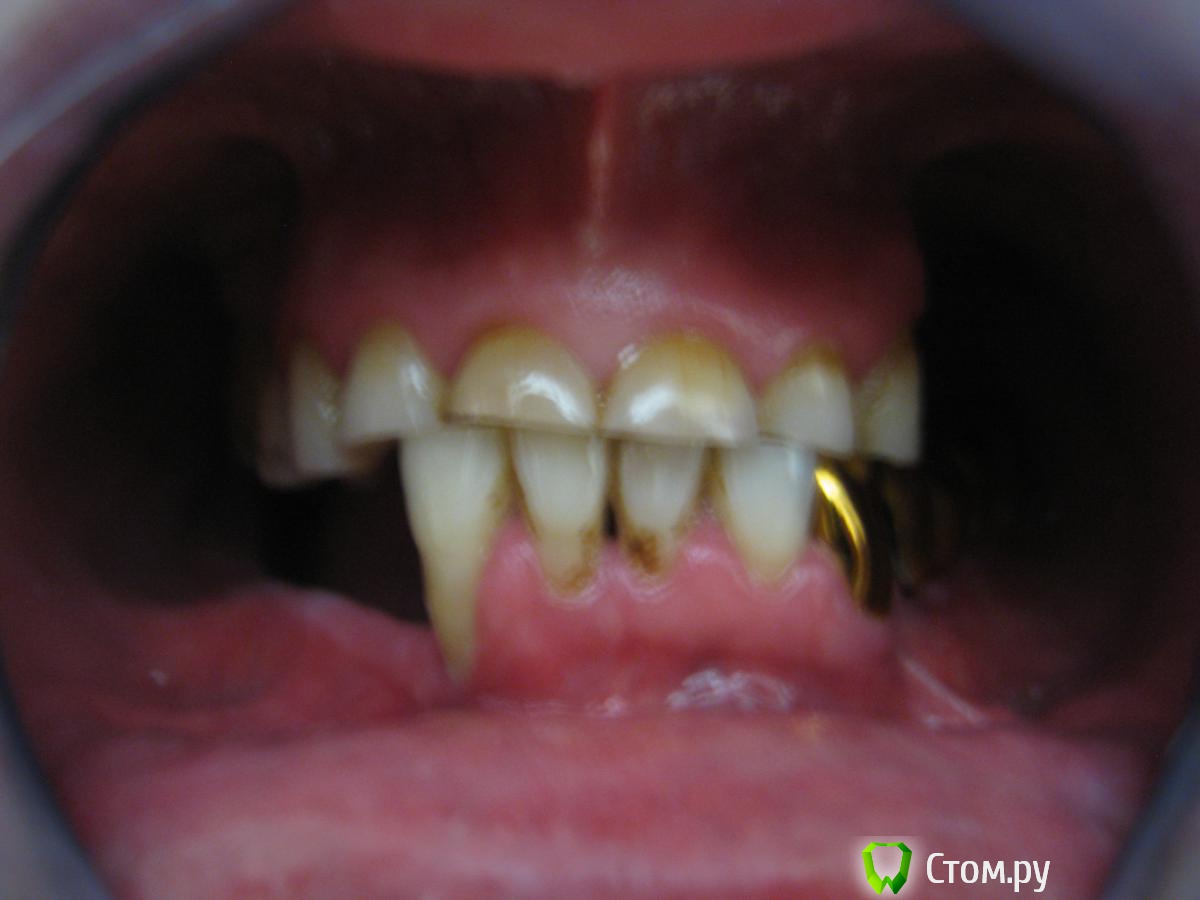

Пациент 49 лет, пришел в клинику с жалобами на боли 21 зуба при накусывании, также хочет протезироваться, зуб 21 поставлен диагноз травматический периодонтит. По словам пациента фронтальные зубы стерлись в течении 3х лет, жевал только фронтом. Коллеги что посоветуете с протезированием? Извиняюсь за качество снимков, Спасибо.